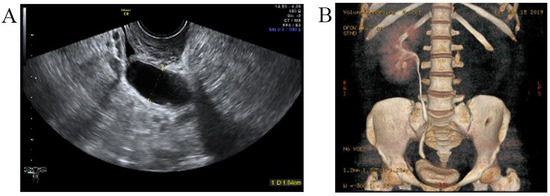

A three-dimensional transvaginal ultrasound revealed adenomyosis and a septate uterus (Figure 1). Two cystic masses with thick internal fluid measuring 3.7 × 4.2 × 2.7 cm (Figure 1A) and 7.5 × 3.1 × 2.1 cm (Figure 1B) were seen on the right side of the uterus, respectively. These cystic masses were considered to be a hydroureter with vaginal fistula. A urinary tract ultrasound revealed the absence of a right kidney, as well as a dilated right ureter measuring 11.1 × 1.8 cm with an ectopic opening into the right vagina (Figure 2A). A computed tomography urography (CTU) revealed the absence of the right kidney (Figure 2B). A pelvic MRI showed a cystic mass considered to be a mesonephric cyst on the right side of the pelvis, bladder, and urethra (Figure 3A). A complete septate uterus with multiple fibroids was also found (Figure 3B). The creatinine concentration of the fluid inside the pelvic cyst was measured to be 157 nmol/L via transvaginal aspiration (Figure 4).

Figure 1.

Three−dimensional transvaginal ultrasound. (A) Transvaginal ultrasound demonstrated a cystic mass with thick internal fluid measuring 3.7 × 4.2 × 2.7 cm on the right side of the cervix. (B) Transvaginal ultrasound demonstrating a cystic mass measuring 7.5 × 3.1× 2.1 cm was seen next to the right side of uterus and its opening into right vaginal wall.

Figure 2.

Malformations of the urinary tract. (A) Urinary tract ultrasound demonstrated the absence of right kidney, right ureteral dilatation, and right ectopic ureter. (B) CTU demonstrated the absence of right kidney.